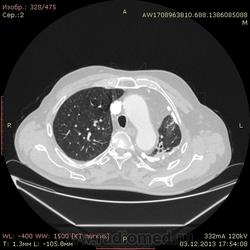

Ребята, вы что, какая жидкость? Чистая известь, посмотрите в костном окне. Отставить натив (в данном случае, хотя для аневризм он обычно нужен). Отставить тромбоз верхней полой вены (потоковые артефакты, не дело вены в артериальную фазу оценивать). Отставить аневризму  аорты, поперчник восходящего отдела на уровне легочного ствола 42мм. А вот легочная гипертензия, здравствуй: поперечник легочного ствола - 37мм, ПЛА - 25мм, ЛЛА - 25мм, НАо - 25-34мм.

Уважаемый коллега Johnnye60! По - моему кальциноз плевры, к контрастированию имеет отношение  только потому, что частично сохраняется жидкость между кальцинированными листками плевры. И если был бы натив - вопросов было бы меньше.

Для справки: холестериновые камни имеют плотность менее 100 ед.Н. Имеющаяся хренотень в левом гемитораксе имеет плотность больше костной, до 1500 ед.Н. Вопрос: какая химико-физико-биологическая реакция может способствовать превращению мягинькаво холестерина в термоядерную плевральную лепёшку?)